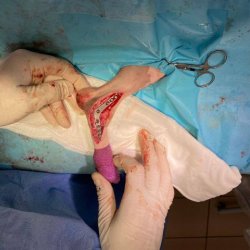

Dasty na operaci s nohou

Dastíka už všichni znáte. Je to svěřenec neziskové organizace Pro psí duši, z.s., kterému jsme přispívali na amputaci ocásku v květnu tohoto roku. Již v květnu RTG u Dastíka odhalil, že měl zlomenou páteř a jeho zadní nožky, pravděpodobně právě po zranění páteře, zůstaly ochromené. Tím došlo k atrofii svalstva, uvolnění šlach u úponů k prstíkům na zadních nožkách. Dasty se nemohl na nožičky normálně postavit a chodil po patách. Nyní je Dasty po operaci první nožičky. Operace byla velikým a nákladným zákrokem. Dasty je ovšem obrovský bojovník s pravým psím srdíčkem. Na listopad je naplánovaná operace druhé nožičky.